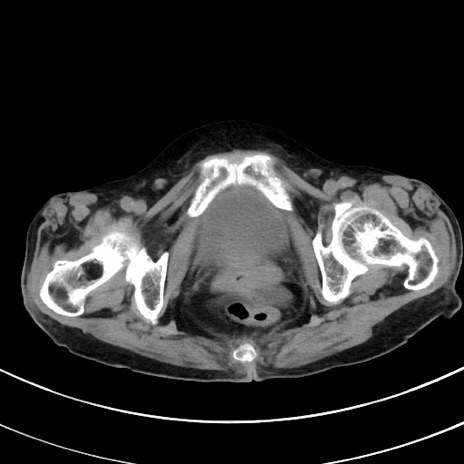

症例33(横断像)

【症例】70歳代 女性

【主訴】心窩部痛

【現病歴】延髄病変の精査・加療にて神経内科入院中。本日より心窩部痛あり。

【既往歴】虫垂炎

【身体所見】右下腹部を中心に圧痛と反跳痛あり。

【データ】WBC 10900、CRP 0.02